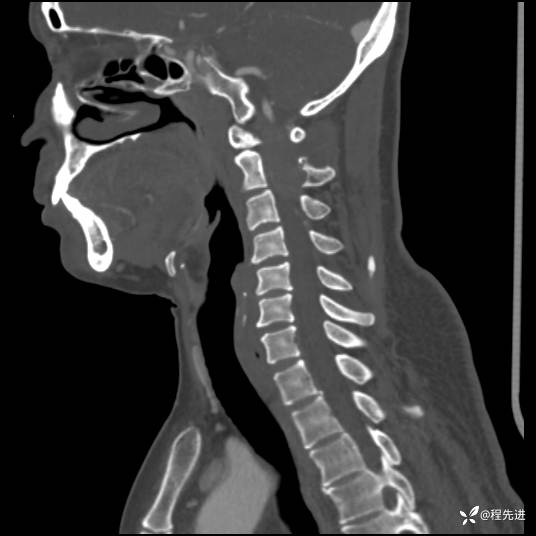

CT平扫+增强: